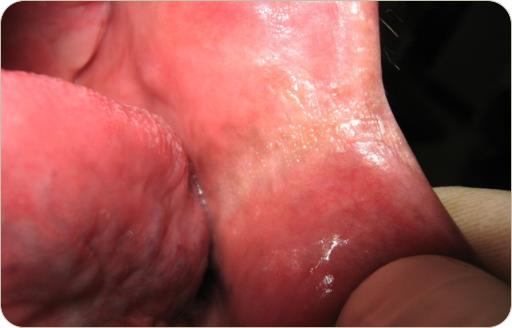

En este mes tenemos tres casos, dos son clínicos y uno es radiográfico, esperamos tu participacion al correo patobu1@hotmail.com o